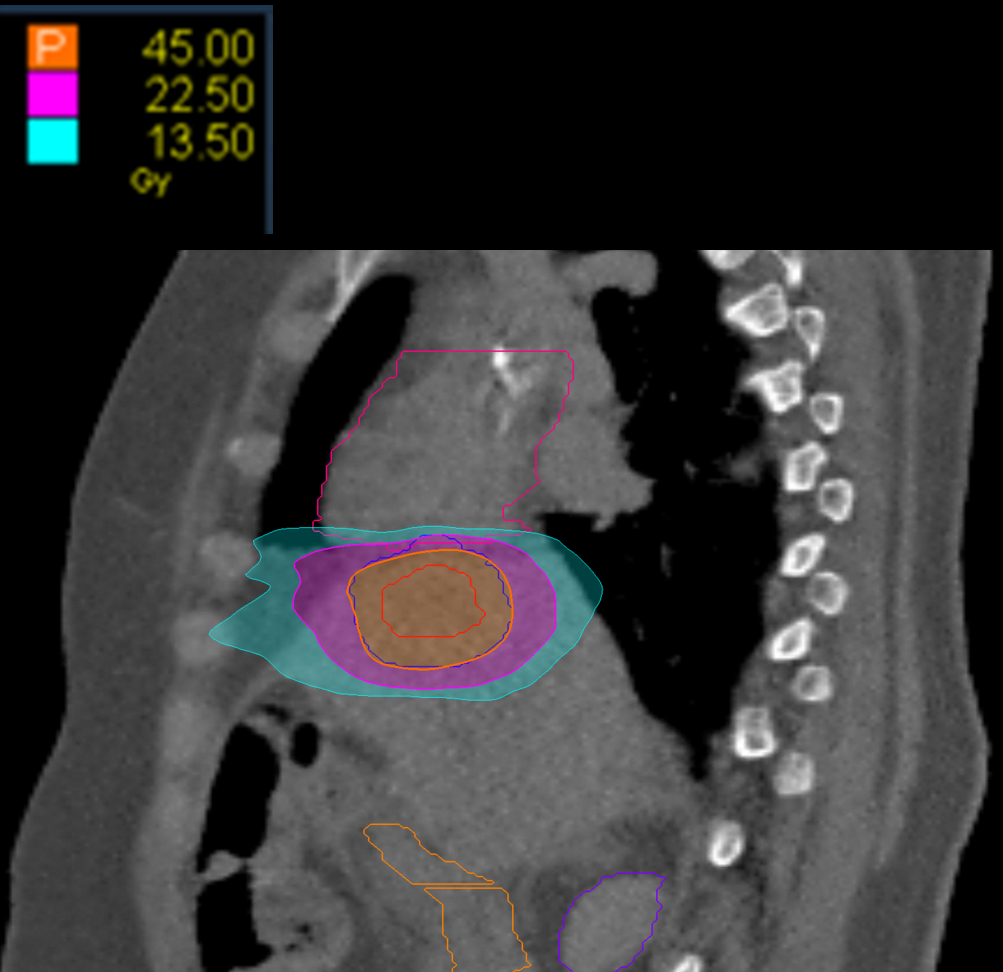

Treatment Plan Images

Fractionation

45 Gy in 3 fractions

PTV(s) Volume

PTV, 34.44 cc

Dose Distributions

- Prescription to the

70.7% isodose line - Max. dose 63.7 Gy

New Conformality Index (nCI)

nCi = 1.11

Gradient Index (GI)

GI = 2.83